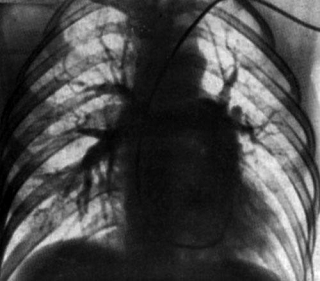

Рис.

Гипоплазия левого легкого. Обеднение сосудов

слева, уменьшение размеров корня, смещение срединной тени.

Кистозная гипоплазия верхней доли правого

легкого. Передне-задняя бронхограмма